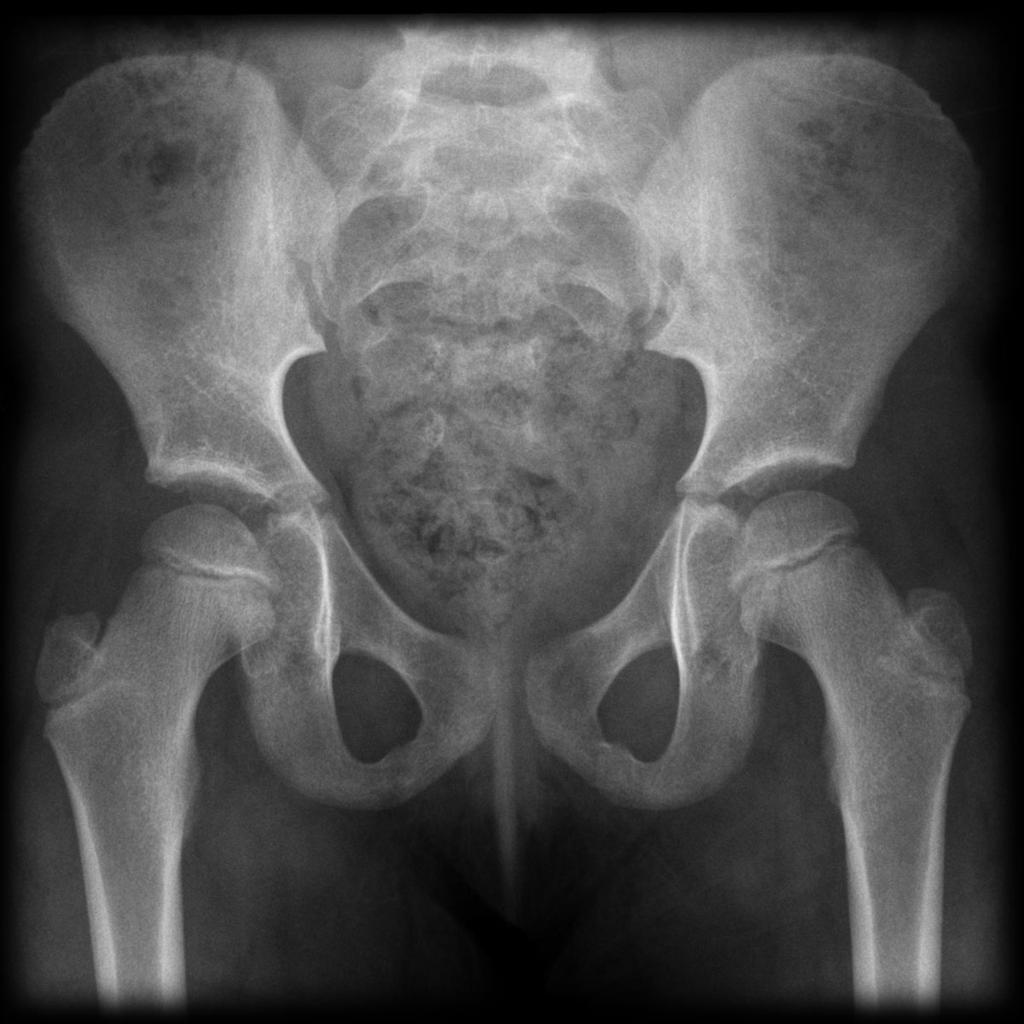

Pelvic Radiography Unnecessary in Children if CT Is Planned